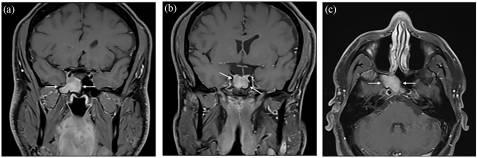

2022年9月,患者接受了鼻窦MRI检查,报告为:右侧蝶窦肿物30×20mm,右侧海绵窦延伸,右颈内动脉180°包绕,直径不变。病变向后侵犯蝶鞍,无法与垂体区分,垂体柄轻微向左偏移。病变完全占据蝶鞍,T2时呈等强度至低强度(图1)。病变具有非特异性信号特征。鉴别诊断包括非典型蝶骨脑膜瘤、低级别癌或淋巴瘤,血管瘤或囊性腺瘤的可能性较小。

图1 术前MRI。冠状(a,b)和轴位(c)T1钆后MRI显示肿物增强,累及右侧蝶鞍下外侧,并延伸至蝶窦右侧隐窝和海绵窦